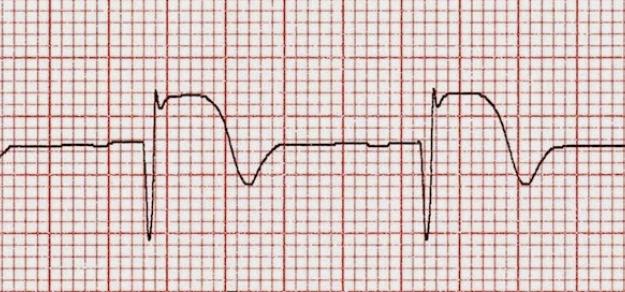

Pacientes con infarto agudo derivados a centros de hemodinamia en Argentina

19 septiembre 2017

Uno de cada tres pacientes es derivado para reperfusión miocárdica, pero los derivados tienen menor probabilidad de recibir tratamiento de reperfusión y menor utilización de angioplastia primaria. Una mejor articulación de las redes podría mejorar el acceso y disminuir la morbimortalidad. Revista Argentina de Cardiología, 2017 Nº 2